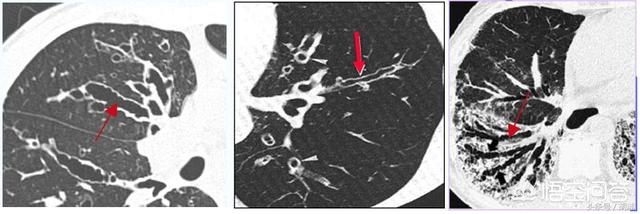

支气管扩张是一种气管结构破坏性疾病,大部分是继发性的,很多是其他疾病特别是感染性疾病的后遗症,有些则是间质性肺病之类的肺部疾病中气管受到被动牵拉造成。这个疾病本身不仅仅是支气管管腔的增大,更重要的是气管内部特别是气管壁上内衬的假复层纤毛柱状上皮的破坏,令支气管乃至周围肺组织完善的微环境受到损伤,失去对外界细菌的免疫功能,从而导致一系列症候群。下面和大家一起学习一下这个疾病。